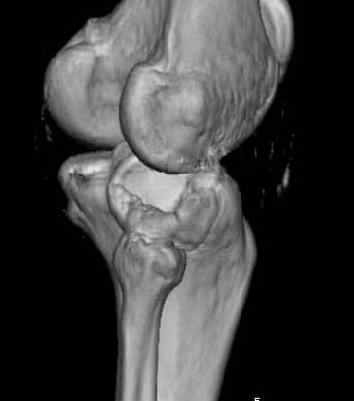

Здравствуйте, уважаемые коллеги!Подскажите, пожалуйста, какой выбрать доступ и способ фиксации при импрессионном переломе заднего отдела наружного мыщелка большеберцовой кости. Женщина 40 лет, травму получила 02.01.2008, катаясь на горных лыжах.Есть ли здесь необходимость использовать задний доступ, или можно справиться через наружный? Есть ли шансы сделать закрыто - под ЭОП через медиальное "окошко" поднять забойником суставную поврехность? Какой лучше использовать фиксатор?Спасибо.

Из медиального окна можно приподнять латеральную

импрессию. Фиксация тремя параллельными шурупами в

эпифизарной части над импрессией. Создается крыша,

которая предупредит коллапс. На образовавшуюся полость - костная пластика из аутокости или синтетический заменитель. Мы применяем Osteoset в 4-5 мм диаметре таблеточки или иньекционную форму Prodens.